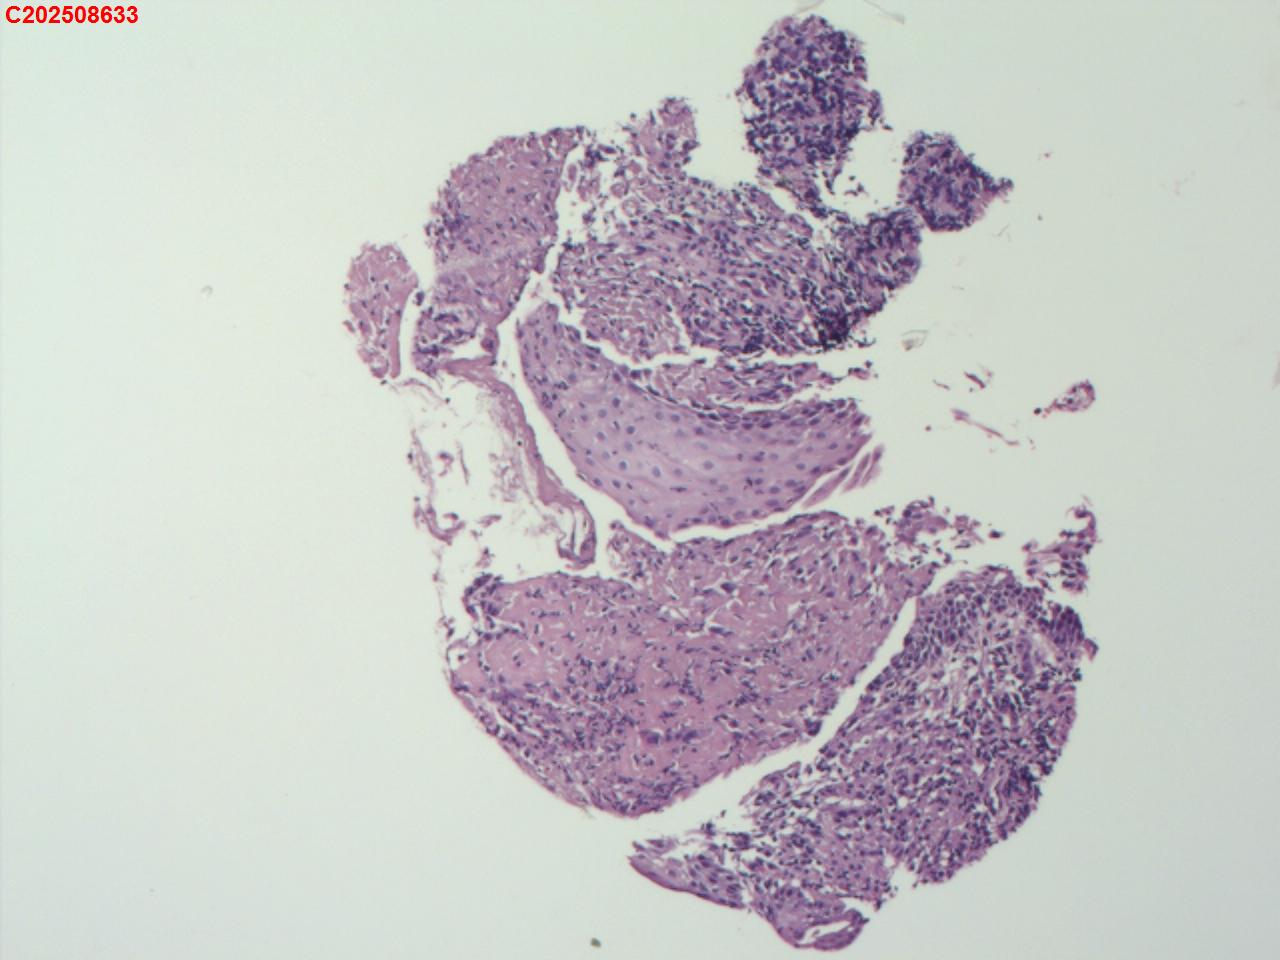

性别年龄82岁临床诊断肺结核?肿瘤?肺部感染?

一般病史2025-07-24 CT检查:考虑右肺上叶炎症伴肺实变,右肺上叶前段支气管显示不明确,建议治疗后复查或支气管镜检查。纵膈多发淋巴结增大。右侧胸腔积液。

标本名称纤支镜咬检

大体所见2025-07-25 气管镜检查示:左侧主支气管、上叶、下叶及各段支气管未见异常。右侧主支气管未见异常。右侧中间段支气管可见碳沫沉积。右肺上叶前段支气管开口可见脓苔附着,支气管开口狭窄,内可见灰黑色新生物阻塞右肺上叶前段支气管管腔。2025-07-25结核感染T细胞检测阳性。2025-07-27肺泡灌洗液查结核分枝杆菌复合群阳性。

坏死物比较多,没有看到明确的肿瘤性病变,可以考虑给一个描述性诊断。